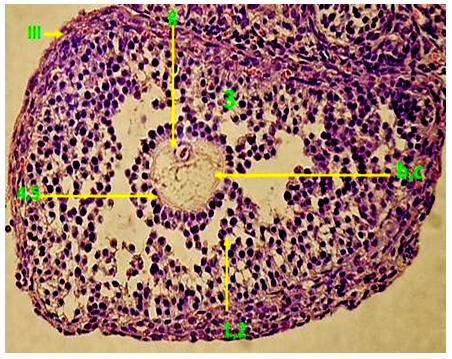

4. Fifteen days after drug Adriamycin injection, with a continues oral administration preventive dose, (H+A-IV) Graafian follicles seem normal and almost complete. However, there have been a few layers of the Granulosa cells. In addition, the oocytes are normal with few fatty gaps as compared with the control group. The number of complete Graafian follicles in the different ovaries is between little and medium, whereas the size of these follicles is larger than those of the control group (fig. 17). In addition, the divisive ability in these follicles seems to be normal as compared with the control (fig. 18).

Fig. 17: Transverse section in recuperative full Graafian follicles in females injected with the drug and administrated with the preventive dose (The fourth time (H+A-VI)-(H & Ix200) Fig. 18: Transverse section in recuperative full Graafian follicles in females injected with the drug and administrated with the preventive dose) the fourth time (H+A-VI)-(Ki67x200)